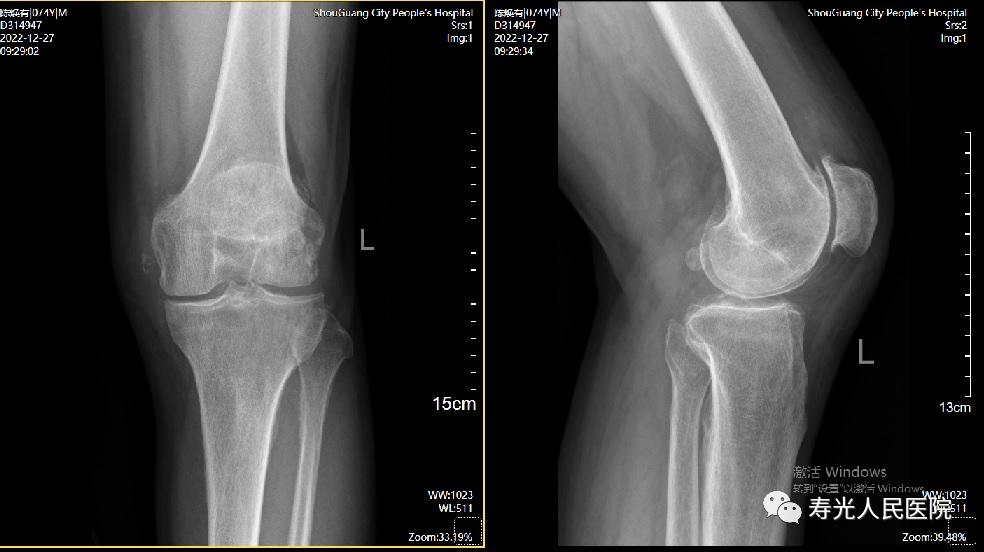

术前影像